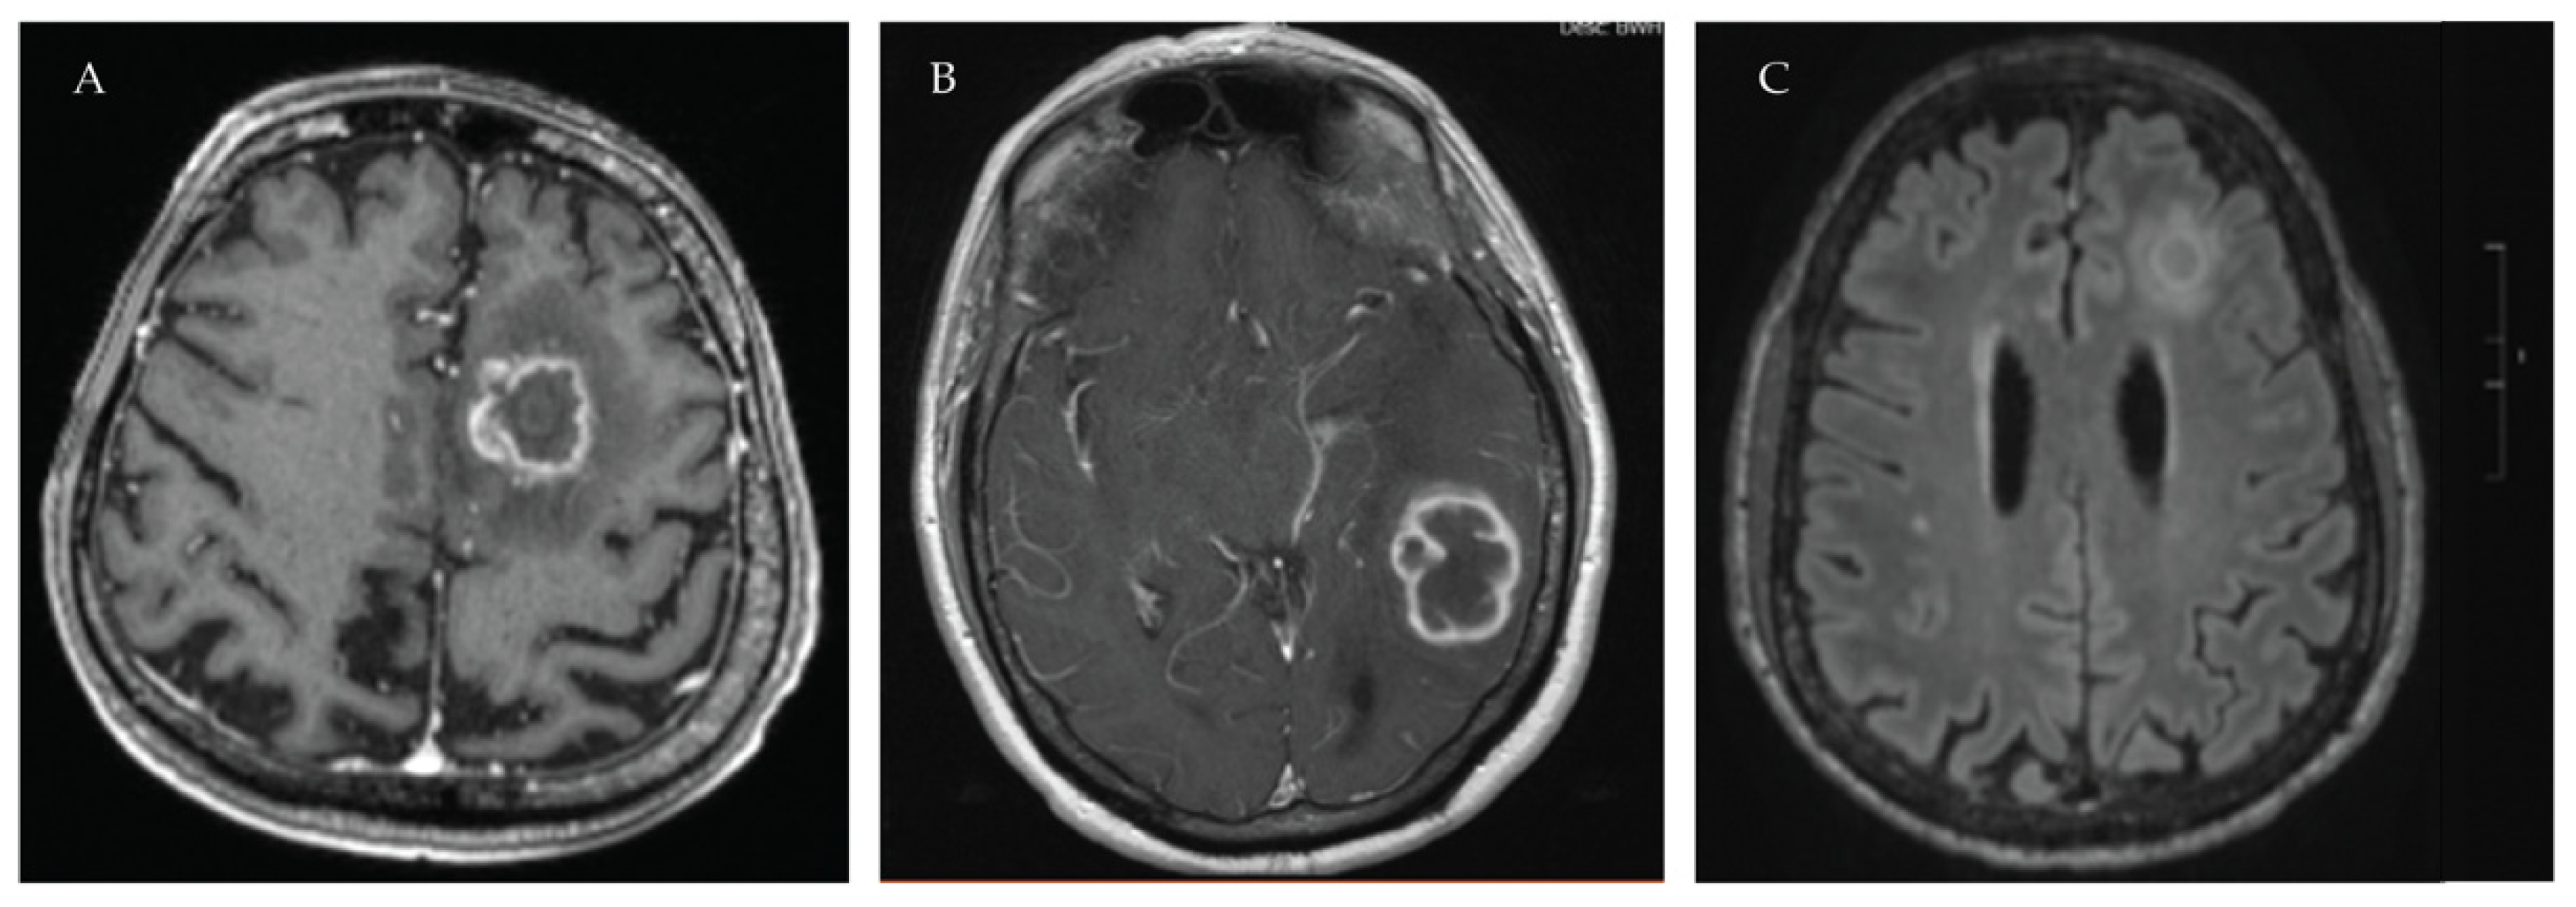

- Lionakis, M.S.; Dunleavy, K.; Roschewski, M.; Widemann, B.C.; Butman, J.A.; Schmitz, R.; Yang, Y.; Cole, D.E.; Melani, C.; Higham, C.S.; et al. Inhibition of B Cell Receptor Signaling by Ibrutinib in Primary CNS Lymphoma. Cancer Cell 2017, 31, 833–843.e5. [Google Scholar] [CrossRef]

- Ghez, D.; Calleja, A.; Protin, C.; Baron, M.; Ledoux, M.P.; Damaj, G.; Dupont, M.; Dreyfus, B.; Ferrant, E.; Herbaux, C.; et al. Early-onset invasive aspergillosis and other fungal infections in patients treated with ibrutinib. Blood 2018, 131, 1955–1959. [Google Scholar] [CrossRef]

| BTK | PCNSL | Lionakis et al. | [63] | IFI incidence 44%; 7 cases of IA including 2 involving CNS; 1 PJP |

| CLL NHL | Ghez et al. | [65] | 33 cases of IFI amongst 16 centers over 4 years; 27 cases IA with 11 involving CNS; 4 cryptococcosis; 1 PJP | |